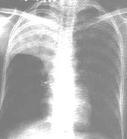

1、大葉性乾酪樣肺炎

(1)整個肺葉或肺段實變。

(2)早期密度可均勻,見壞死溶解成不規則的蟲蝕樣空洞。

(3)肺葉體積常因肺組織廣泛破壞而縮小。

(4)其他肺野可有支氣管播散病灶。

(5)短期複查無明顯變化。